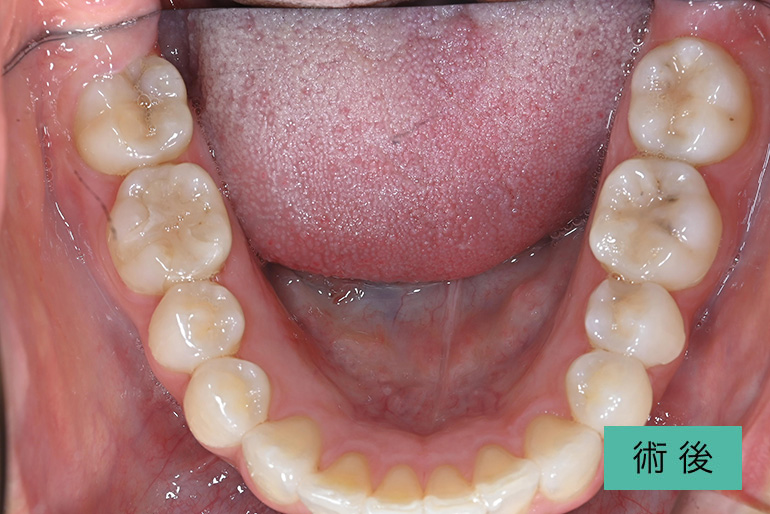

インビザライン②

| 治療内容 | 歯並びをキレイにしたい。 口腔内容積を狭くしないように、歯列を拡大し非抜歯で矯正をする。 |

|---|---|

| 治療期間・回数 | 約3年半、40回 |

| 費用(税込) | ¥880,000(マウスピース矯正) ※自由診療 |

| リスク・副作用 | 歯肉退縮、知覚過敏、後戻り |